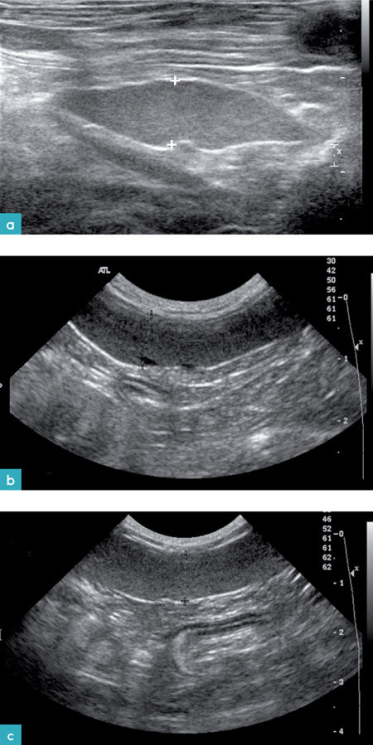

健康动物的脾脏边界清晰,被膜薄而光滑(图2和图3)。脾脏的脏器面的轮廓不规则,是因为在脾门的地方有血管进出。横断面上的脾脏呈三角形(图4)。二维超声图像上很难看到脾动脉进入脾脏,需要使用彩色多普勒才能识别脾动脉(图3)。

最近一项研究提出了判断健康猫脾脏大小和外观评估的新方法(Sayreand Spaulding,2014)。该方法选取脾脏的三个部分进行测量:脾头(近端三分之一)、脾体(中间三分之一部分)和脾尾(远端三分之一部分)。在每个部分测量脾脏的高线(从脏器面到体壁面的垂直距离)。

分别测量脾头和脾尾横截面上的厚度。此时脾脏呈三角形,在脏器面上可见脾脏静脉。把光标放在脏器面上静脉的旁边(但是不要放在血管内),垂直引一条线到达体壁面进行测量,得到脾脏的厚度。要在脾脏的内外侧顶点到达脾门的距离相等的图像上测量脾脏的厚度,避免在斜切面上测量。

在脾脏的长轴(矢状面)上测量牌体的厚度。从脏器面上的血管旁垂直测量到体壁面,得到脾体的厚度(图7)。

脾脏三个不同部位厚度的正常参考值。表1.

最可靠的测量位置是测量脾头,在检测猫脾脏的时候,推荐的方案是:在前三分之一的脾脏横切面上,从脏器面的血管旁测量到体壁面的距离,(正常值为5.4mm9.1mm。如果超过9.1mm),则表示脾肿大,需要结合其他器官的超声表现对病患做全面的评估。也可以通过细针穿刺或活检脾脏,做进一步诊断。其他作者有报道显示:有些猫脾脏肿大的原因是脾脏自身的折转(图 8)。